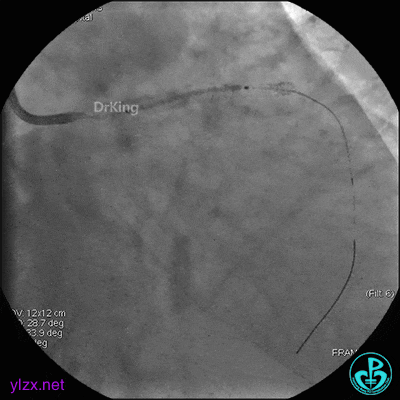

前降支近端串联植入支架,前降支开口支架精确定位。

支架内非顺应性球囊后扩张。

最后造影结果显示前降支3级血流,支架膨胀尚可。